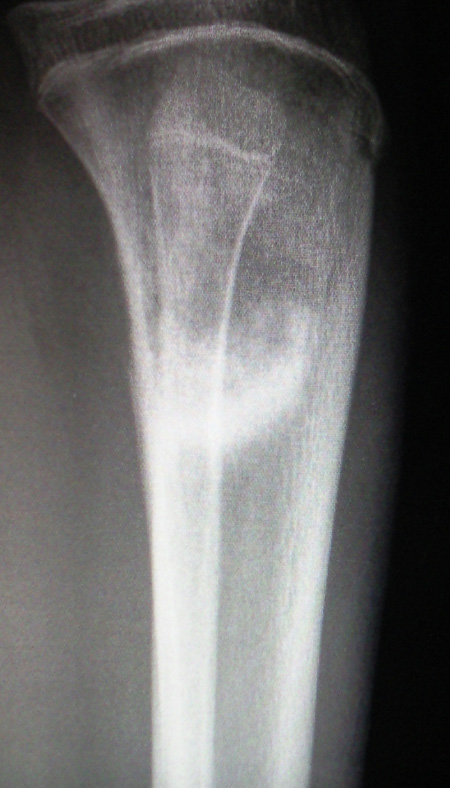

男18m岁,左下肢肿痛四天,体检左下肢肿胀,皮温高,压痛

外缘层状骨膜反应,内缘可见骨质破坏,首先考虑急性化脓性骨髓炎

骨皮质破坏,且见斑状密度增高影。考虑急性骨髓炎。

患者临床病史较短,面骨质改变较明显,显然不符合急性骨髓炎改变。

内侧骨皮质呈明显的破坏征像,不像慢性骨折修复,显然不是彼劳骨折。

骨质破坏,硬化,骨膜反应,患者年龄符合骨肉瘤发病年龄,因此可以考虑,但要排除慢性骨髓炎。

因此本病鉴别在于病史,进一步询问病史,如无确切骨髓炎症史及相应症状等,多考虑骨肉瘤

典型混合型骨肉瘤表现。

支持骨肉瘤。有以下证据:1. 年龄 18岁 (好发年龄10-25岁,20岁左右占3/4) 2. 临床符合 --疼痛和肿胀为常见的表现。局部压痛、皮温升高。3.影像表现符合---较有特征性的改变为骨质增生、以肿瘤性新骨形成为其特点。